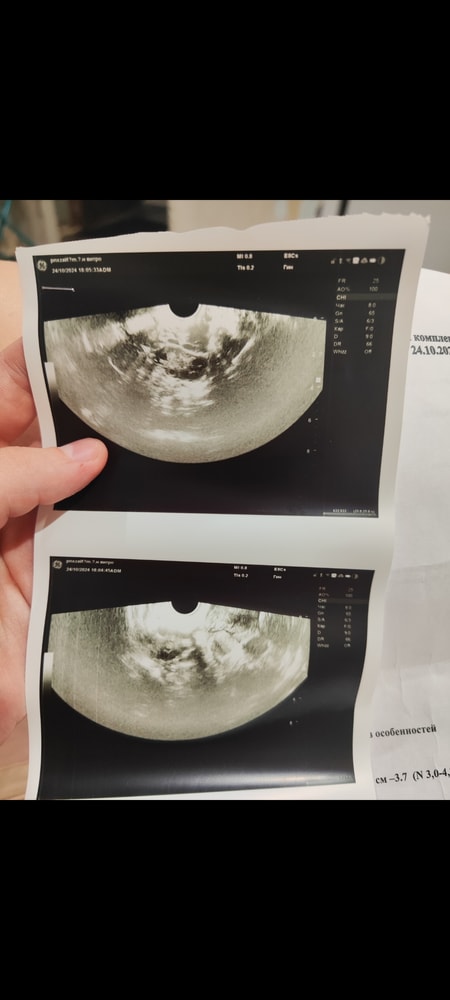

Девчат, привет! Может кто разбирается? Подскажите, пожалуйста, поставили МФЯ и сказали никак не лечить, но я почему-то сомневаюсь что это не ошибка.

Цикл абсолютно нерегулярный, от 30 дней до 115. Действительно ли это МФЯ? Или все-таки обследоваться? (Очень затратно по финансам, сами понимаете, не хочется в пустую отдавать)